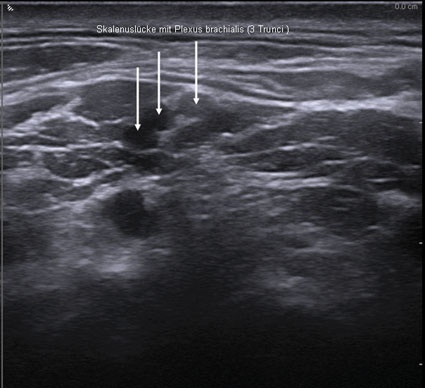

Die sehr hohe Auflösung moderner Ultraschallgeräte bzw. der verwendeten Sonden kann heute nervale Strukturen im Millimeterbereich darstellen. Somit bietet der Ultraschall die Möglichkeit der exakten anatomischen Darstellung von gewünschten nervalen oder vaskulären Strukturen, außerdem ist die Methode unabhängig von Einschränkungen der Nervenfunktion. Bei einer Leitungsanästhesie oder Leitungsblockade werden bestimmte Nerven oder Nervenäste durch Umspritzung mit Lokalanästhetika für die Schmerzleitung ausgeschaltet.

Der Ultraschall ist - insbesondere unter Verwendung hochfrequenter Schallköpfe - hervorragend geeignet zur Darstellung von Nerven und Nervenplexus. Erkennbar sind Nerven an einem typischen Schallmuster, ebenso sind Weichteile und insbesondere Gefäße exakt darstellbar. Voraussetzung für eine korrekte Interpretation sind allerdings Kenntnisse in der optimalen Geräteeinstellung, fundierte Kenntnisse in der Anatomie der entsprechenden Regionen und eine korrekte Punktionstechnik.